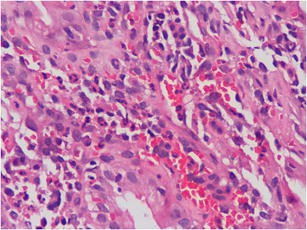

Fig. 1